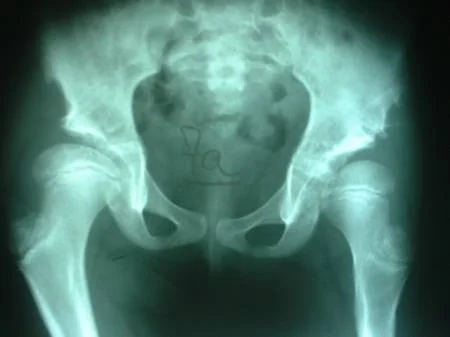

CASO CLINICO: DISPLASIA EVOLUTIVA DE AMBAS CADERAS (LUXADAS)

Paciente femenino de 8 meses de edad, portadora de displasia del desarrollo de ambas caderas (luxadas), intervenida quirúrgicamente por el Dr. Alberto A. Martínez Conde a la edad a la edad de 2 años motivado a que el familiar no acudió a la consulta por 14 meses. Se utilizo la Técnica de Klisic con buenos resultados.